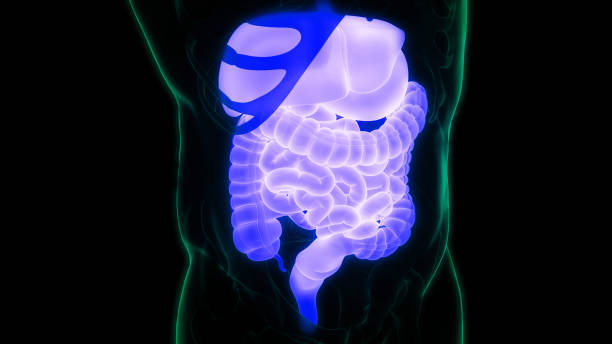

위암은 조기 발견이 생존율을 크게 높일 수 있는 질환입니다.

40세 이상의 모든 국민은 2년에 한 번씩 국가에서 내시경을 통한 건강검진을 받을 수 있으므로 꼭 시기를 놓치지 말고 정기적인 검진을 받는 것이 중요합니다.

현재의 어려운 시기에도 건강을 우선으로 생각하고 검진을 받아보세요.

이렇게 하면 위암을 조기에 발견하여 치료할 기회를 놓치지 않을 것입니다.